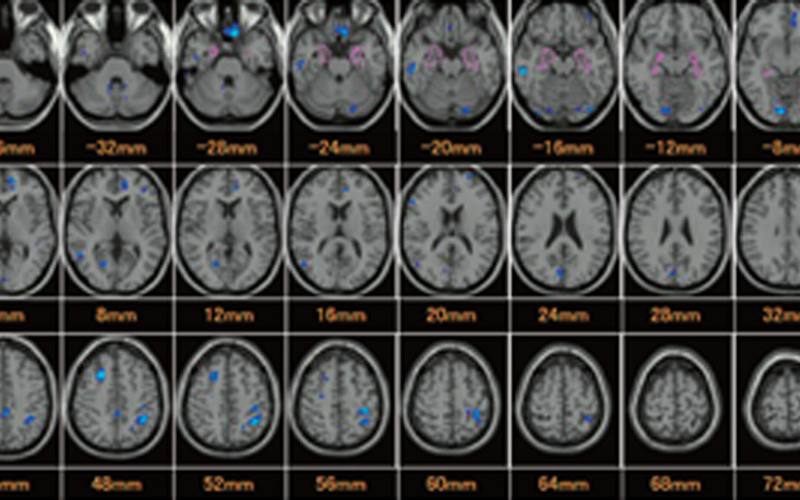

脳ドック・脳委縮定量解析

脳委縮量を定量化することで、アルツハイマー型認知症やレビー小体型認知症などのリスクを評価できます。脳ドックと併用で受けられるので、脳の健康を総合的にチェックできます。